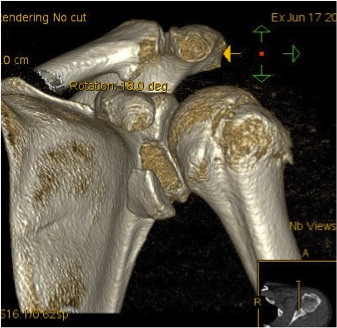

Case 3

Glenoid Malunion

Case 1

- untreated glenoid rim fracture

- patient with chronic instability

- treated with glenoid osteotomy